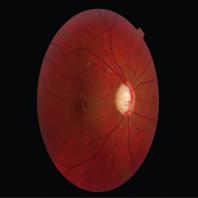

- eCas clinique 10-1A

- eCas clinique 10-1B

- eCas clinique 10-1C

- eCas clinique 10-1D

- eCas clinique 10-1E

- eCas clinique 10-1F

- eCas clinique 10-2A

- eCas clinique 10-2B

- eCas clinique 10-2C

- eCas clinique 10-2D

- eCas clinique 10-3A

- eCas clinique 10-3B

- eCas clinique 10-3C

- eCas clinique 10-3D

- eCas clinique 10-3E

- eCas clinique 10-3F

- eCas clinique 10-3G

- eCas clinique 10-3H

- eCas clinique 10-4A

- eCas clinique 10-4B

- eCas clinique 10-4C

- eCas clinique 10-4D

- eCas clinique 10-4E

- eCas clinique 10-4F

- eCas clinique 10-4G